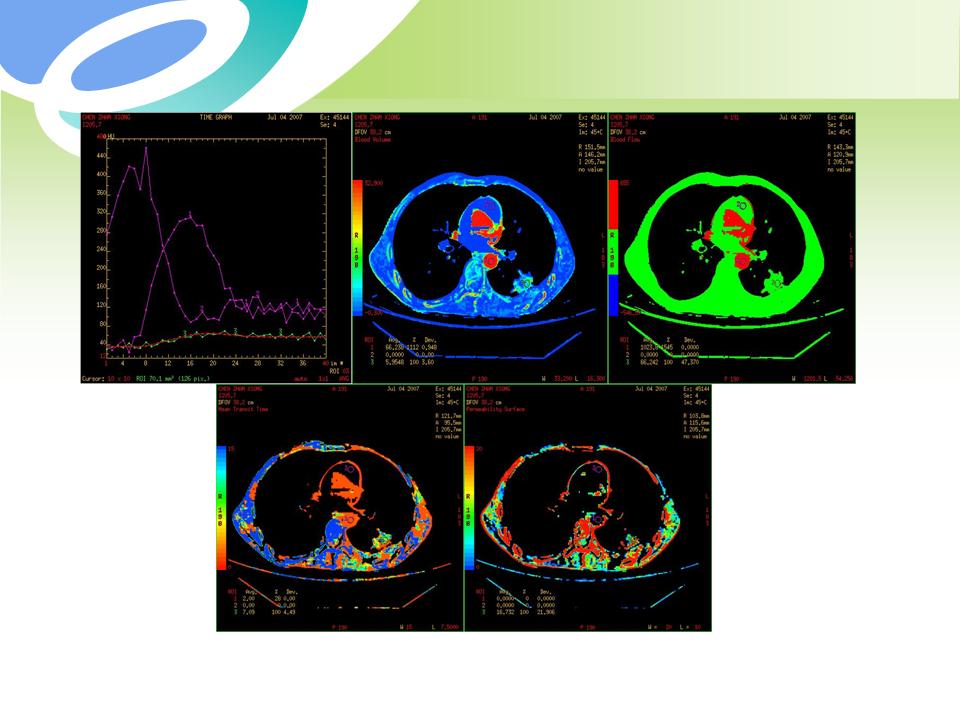

肺部病变的CT基本征象